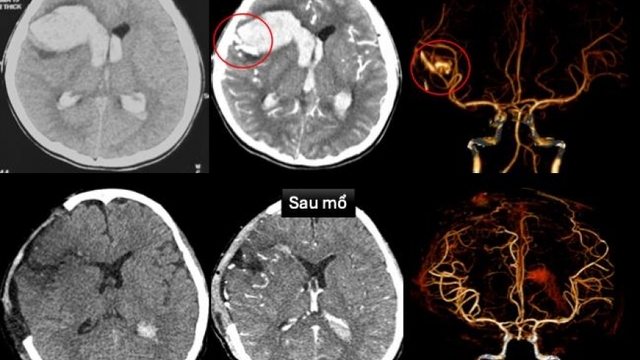

Cứu bệnh nhi bị dị dạng mạch máu não kèm bệnh cơ tim xốp hiếm gặp